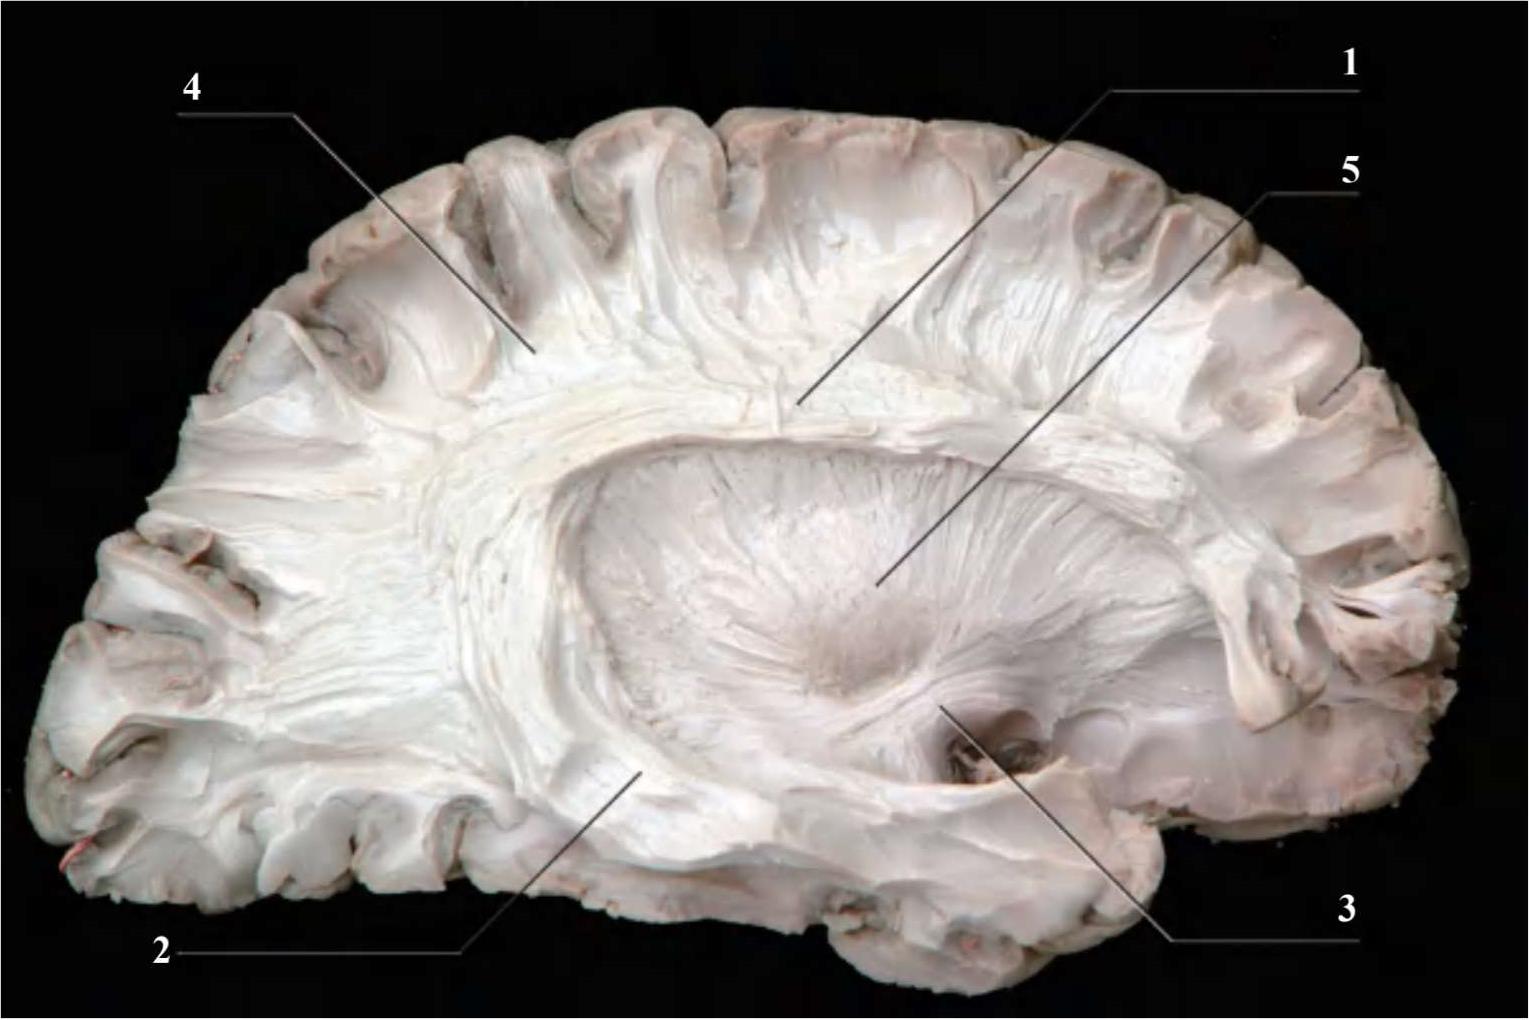

1.上纵束 fasciculus longitudinalis superior;2.下纵束 fasciculus longitudinalis inferior;3.钩束 fasciculus uncinatus;4.大脑弓状纤维 fibrae arcuatae cerebri;5.豆状核 lentiform nucleus

图2-9 联络纤维